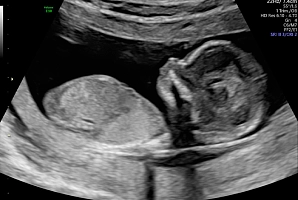

Акушерское УЗИ (1, 2, 3 триместр) в Тюмени

С помощью ультразвукового исследования во время беременности врач может оценить нормальную анатомию плода, размеры органов и структуру, их взаиморасположение, определить маркеры хромосомных патологий или аномалии органов плода, а также строение плаценты, объем околоплодных вод и строение пуповины. Ультразвуковой метод – это основной и первый метод, дающий информацию врачу акушеру-гинекологу и влияющий на результат биохимического скрининга.

УЗИ проводится на сроке 11–14 недель, чтобы:

• оценить анатомию органов плода;

• увидеть грубые пороки развития и / или признаки генетических аномалий (которые потенциально могут потребовать прерывания беременности).